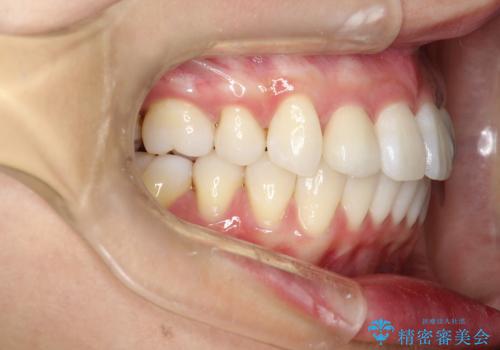

上顎の歯が全体的に前方に位置しているのと、前から2番目の歯が通常よりも小さい矮小歯という状態でした。

出っ歯をなおすために上顎の前から4番目の歯を抜歯して、引っ込めるのと、前から2番目の歯に通常の大きさのオールセラミックを装着して整った歯並びにすることにしました。

歯の大きさが通常と異なる場合は矯正治療で歯並びだけきれいにしても、整わないことがあります。

その場合はセラミックのかぶせ物を装着して歯の形を正常にすることで、さらに整った歯並びにすることができます。